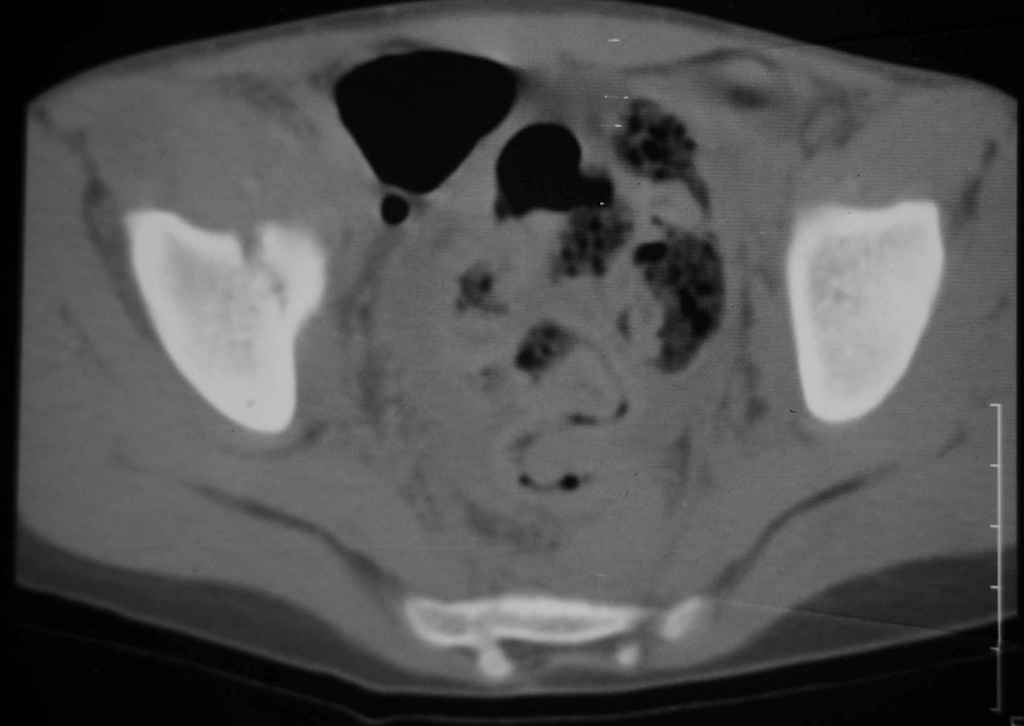

Перелом вертлужной впадины

Уважаемые коллеги, помогите определиться с тактикой лечения. Ребёнок 7 лет, травма 11.09.08, поступил с травматическим вывихом бедренной кости.

Вывих вправлен, конечность фиксирована на скелетном вытяжении. Что делать с переломом подвздошной кости? Лечить консерватино или оперировать?